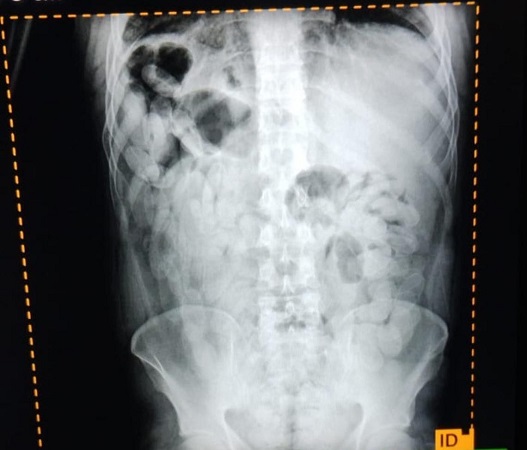

Ante las altas posibilidades de estar frente a la modalidad de traslado de estupefacientes denominada “capsulero” y para preservar la salud de las personas, se solicitó asistencia de emergencia y el traslado al Nosocomio local, en donde mediante placas radiográficas pudieron confirmar la presencia de capsulas.

Luego, los involucrados evacuaron 180 capsulas que sometidas a la prueba de campo narcotest dieron resultado positivo para cocaína con un peso total de 2 kilos 102 gramos.